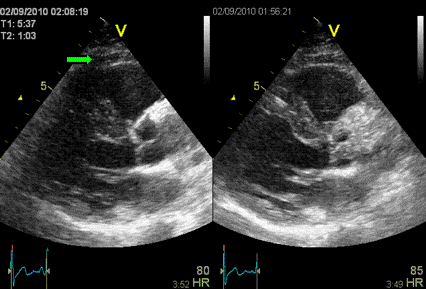

Ультразвуковое исследование (УЗИ)

Сегодня ультразвуковые исследования – нестареющая классика. Метод дает большое количество информации и относится к самым доступным и безопасным. УЗИ проводится для исследования плода, гинекологических, урологических, эндокринных, сосудистых и болезней ЖКТ. Работает УЗИ-аппарат следующим образом: он испускает звуковые волны и по отражению волн определяет границы, плотность и другие характеристики исследуемых органов.

Историческая справкаПуть ультразвука (УЗ) в медицинскую диагностику был тернист. Долгое время ультразвук использовали для поиска дефектов в металле, а в медицину он изначально попал как лечебное физиотерапевтическое средство. В диагностических целях первый раз УЗ применил невролог Карл Дуссик. С его помощью доктор изучал структуры мозга у человека. Как это часто бывает, первый блин вышел комом: врач неверно интерпретировал результаты, сочтя кость черепа мягкой опухолью. Зато вторая попытка прошла вполне удачно. В 1949 г. Джон Уайлд с помощью УЗИ смог правильно оценить толщину стенок кишечника у своего пациента.

-9

В случае УЗИ качество диагностики зависит и от аппарата, и от умений врача. Так, опытный специалист, используя систему последнего поколения, сможет заподозрить опухолевый процесс даже на самой начальной стадии. Из-за своей безвредности УЗИ активно применяется у детей и беременных и как дополнительный метод к другим, более «тяжелым» видам сканирования.